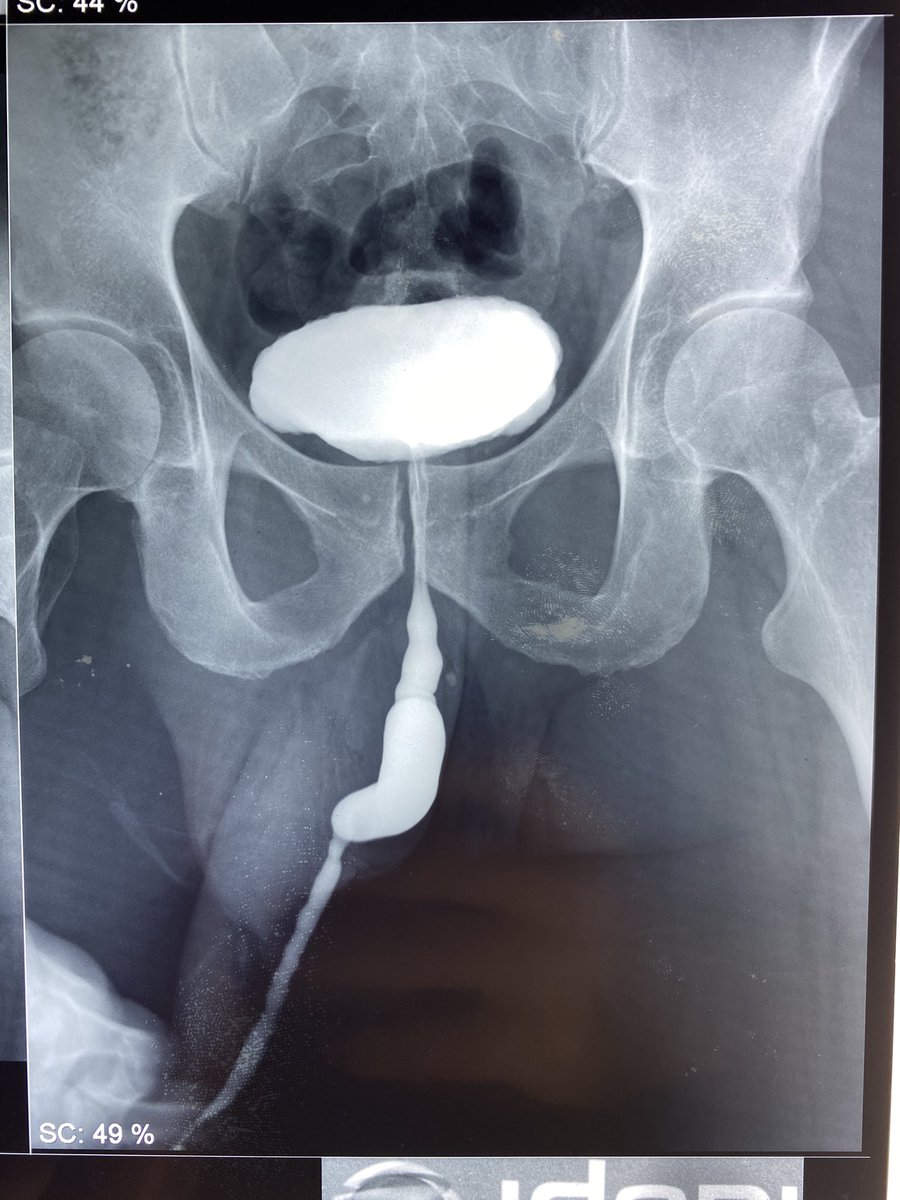

@Lfsala

Foreign body of the bladder ⁦